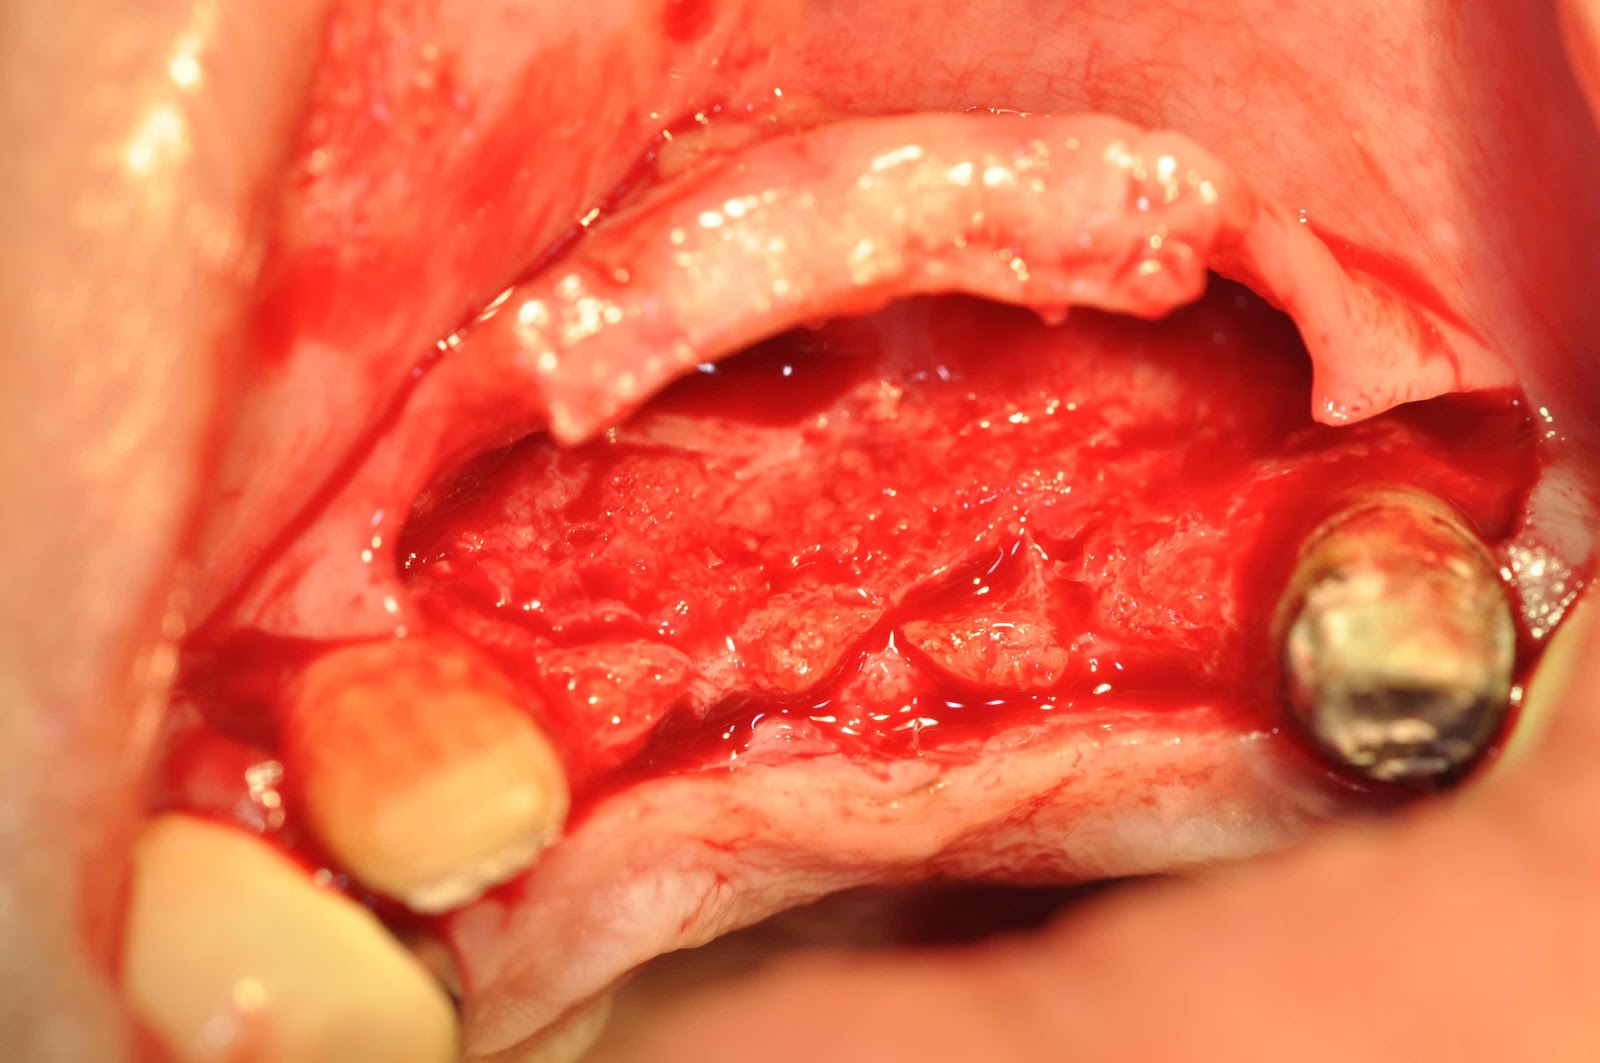

臨床上遇到這種因意外導致失去前牙所產生的‘絕壁’,最好的方法就是先自體骨塊移,3-4個月後再植入人工牙根,本例在預定置入植體處放置自體骨塊,而骨塊與骨塊之間使用人工骨粉填空,三個月後可以看到骨塊與骨粉與身體的整合,雖然多了一個取骨區疼痛,但是,俗話說的好No pain,No gain(沒有痛苦就沒有收穫),大量骨缺損還是建議使用Real Bone。